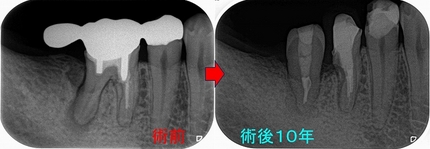

破折歯の残し方

50代以降に増えてくる歯根破折

歯根破折は歯ぎしりが見られる方の奥歯によく見られます。

患者さんは50代女性

歯茎の下に虫歯があるということで治療を行いクラウンを入れた。

普通にしていれば痛くはないが歯茎が腫れてきた。また咬んだ際に痛みがある。

先生には次に腫れたら抜歯と言われている。

レントゲン

2026 EEdental NAM (1).jpg

近心根が折れているような所見があり、根尖にはファイル(金属ヤスリ)破折が2本見られます。

患者さんには、折れており保存治療は難しいこと

保存を行おうとすれば、「接着修復」←私はやっていない(正確に言うと才能なく辞めた)

私が出来るのはヘミセクション(分割抜歯)ぐらい・・・

患者さんにOKをもらい

2026 EEdental NAM (2).jpg

まずは根管治療を行い

折れた歯の分割抜歯

一般的にはブリッジにするケースですが、個人的には1本で支え使える所まで使ってもらいます。

2026 EEdental NAM (3).jpg

仮歯で経過を見て、問題無さそうなので

硬質レジンでクラウンを作ります。

2026 EEdental NAM (4).jpg

レジンでクラウン作る理由は柔らかいから、ここにジルコニアなどの固い物をでクラウンを作ると

根の方に負担がかかり、すぐにダメになった経験があるので、わざとクラウンは弱目の材料を使い

クラウンをすり減らし、根の方への負担を軽減させます。

ホント歯根破折は人生の後半の方になってくると避けては通れない問題になってきますね・・・